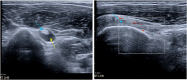

The rotator cuff is a group of four muscles and tendons surrounding the shoulder joint providing it strength and stability. The rotator cuff consists of the subscapularis, supraspinatus, infraspinatus and teres minor. Many shoulder complaints are caused by rotator cuff pathology such as impingement syndrome, tendon tears and other diseases e.g. calcific tendonitis. Diagnosis starts with clinical history and physical examination, after which imaging is often used to help confirm clinical findings depending on the differential diagnosis. The aim of the article is to review the frequently used imaging modalities to assess the rotator cuff and cuff-related disease, specifically focusing on radiography, ultrasonography and magnetic resonance imaging. This article will outline the advantages and disadvantages for each modality and illustrate typical radiological findings of common rotator cuff pathologies.